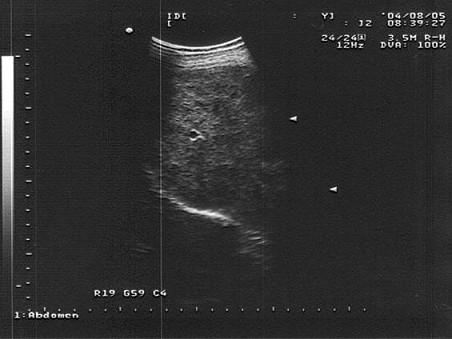

问题 男,48岁,上腹胀痛,纳差,血吸虫病多年。结合超声声像图,诊断为?(?)

选项 A.血吸虫肝纤维化 B.脂肪肝 C.细菌性肝脓疡 D.肝豆状核变性 E.肝炎

答案 A